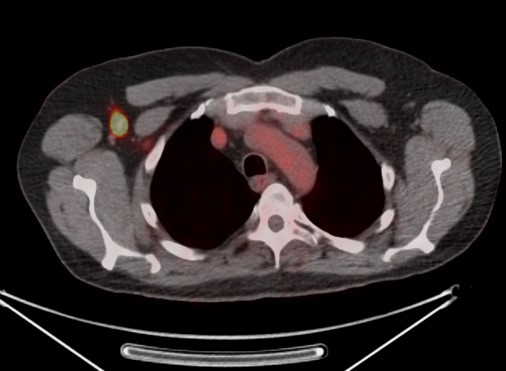

Fused axial FDG PET-CT (B), PET axial (C), CT axial (D) and MIP PET (E) images demonstrate intensely FDG avid lymph node in the right axilla. Infiltration of FDG at the injection site in right antecubital fossa results in lymphoscintigraphy with FDG migrating to the regional nodal basin via the lymphatic ducts. |

| Fused axial FDG PET-CT (B), PET axial (C), CT axial (D) and MIP PET (E) images, demonstrate intensely FDG avid lymph node in the right axilla. Infiltration of FDG at the injection site in right antecubital fossa results in lymphoscintigraphy with FDG migrating to the regional nodal basin via the lymphatic ducts. |